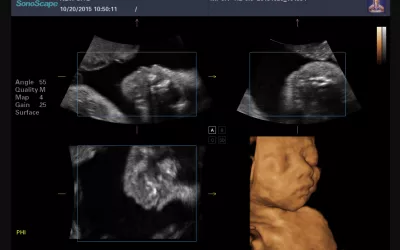

BrightHeart is an AI-powered medical device designed to support gynecologists, obstetricians, and sonographers during prenatal ultrasound exams. Its focus is on one of the most complex and most frequently missed areas of prenatal screening: congenital heart defects (CHD).

BrightHeart’s workflow solution uses AI to guide clinicians through the ultrasound exam, helping them capture the right views, validate exam completeness, and flag potential abnormalities without disrupting existing workflows.

BrightHeart’s technology is designed to fit seamlessly into existing clinical environments. The system relied on a tablet placed next to the ultrasound machine, connected securely to the cloud. During the exam, the software guides the sonographer through a structured checklist, ensuring all required views are captured.

The AI analyzes eight key pathological markers, using a color-coded system to indicate whether findings are normal, abnormal, or require further attention. This not only improved detection, but also reduced the need to recall patients due to incomplete exams - a major operational and emotional burden in prenatal care.

Importantly, BrightHeart does not provide a diagnosis. It functions as a clinical decision-support tool. If warning signs appear, patients are referred to pediatric cardiologists for definitive diagnosis and care planning, including decisions about delivery in specialized Level 3 maternity units when needed.